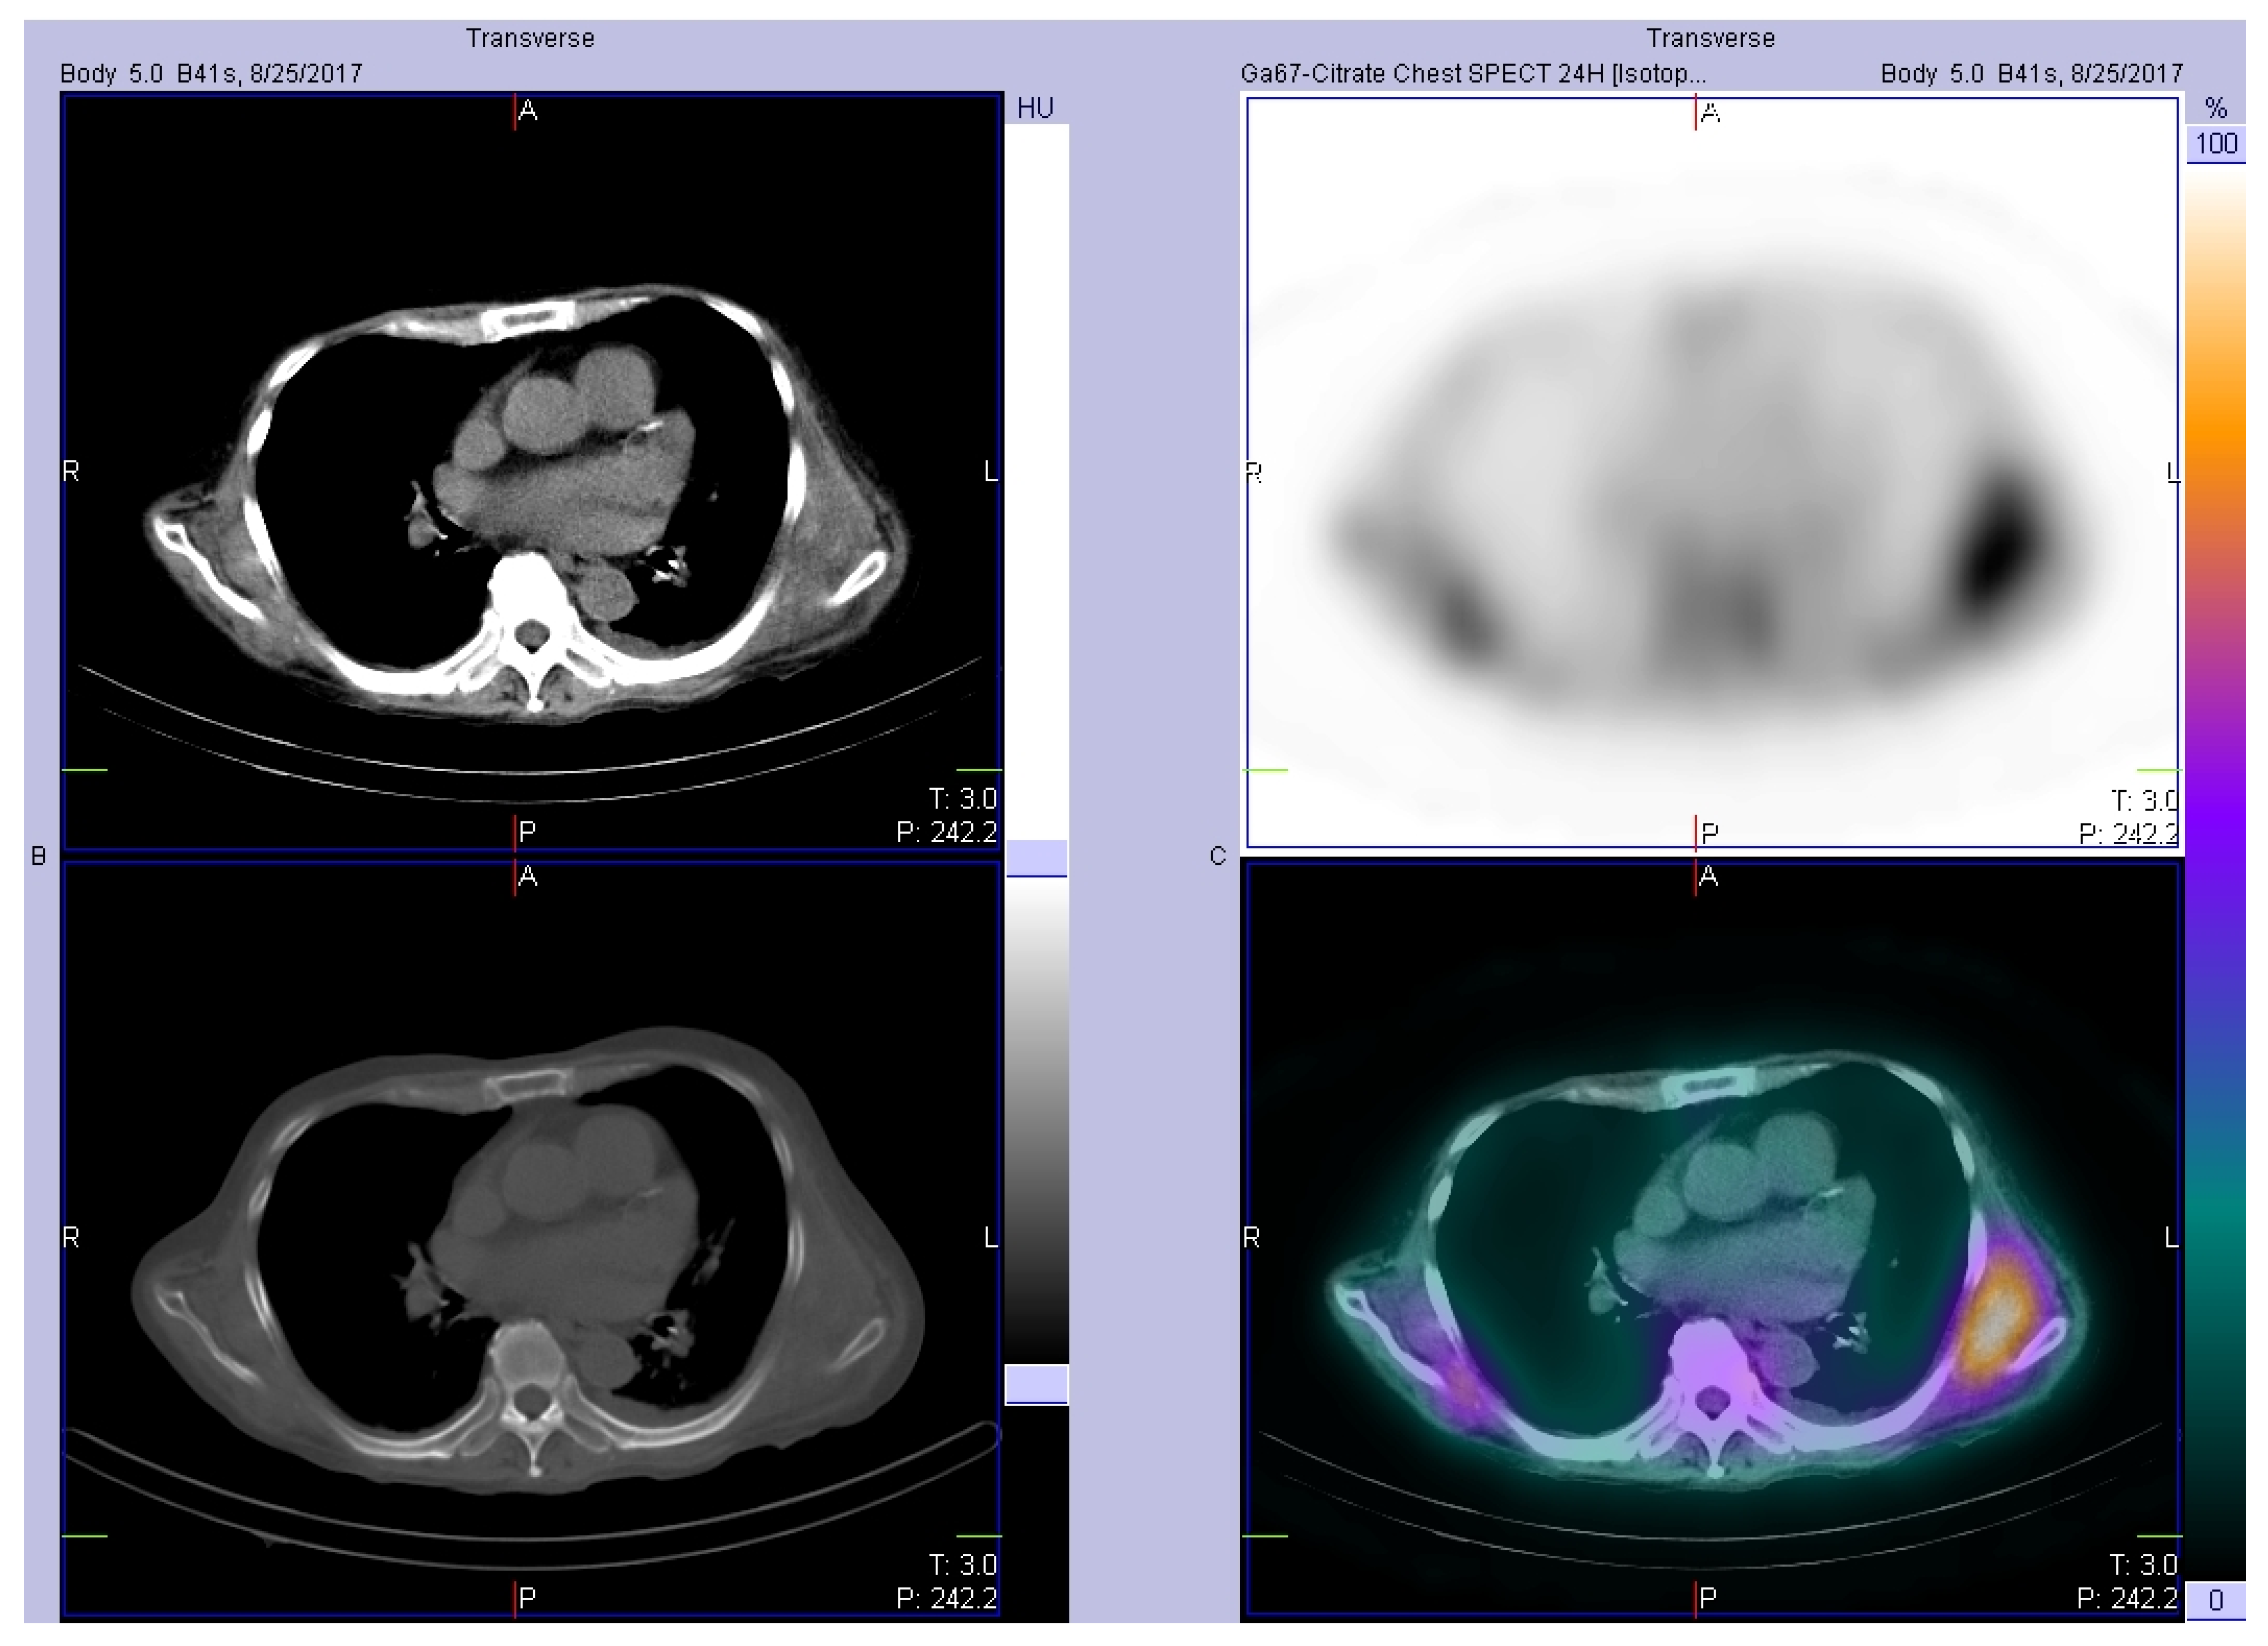

2. Case Report